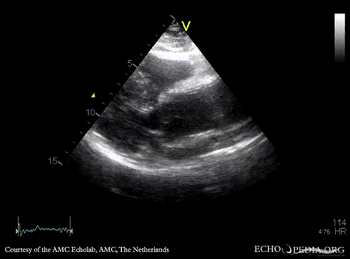

30 Aortic dissection

E00243.gif E00244.gif

PLAX: dilated aortic root and ascending aorta PLAX: Color Doppler, mild aortic regurgitation